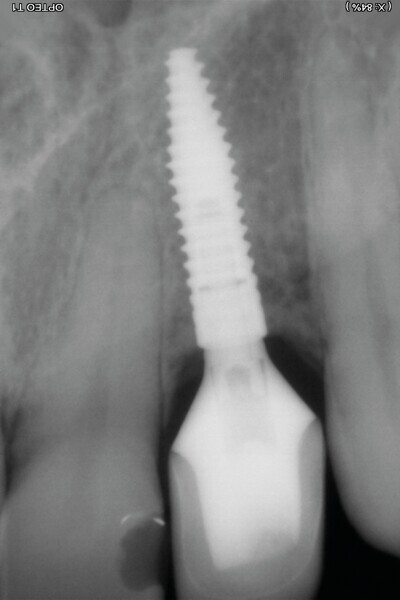

Il ne faut surtout pas être piégé par la hauteur d’os perdu et enfouir plus l’implant. Un tissue level est parfaitement stabilisé grâce à ses dernières spires. (Implant TL Straumann SP 4,1 RN, longueur 12 mm SLActive). Une incision limitée en étendue et en forme de « H » est réalisée dans le secteur de la dent de sagesse inférieure, pour un abord crestal. Un trépan de diamètre supérieur au trépan de calibrage (Fig. 5), donc 6 mm dans ce cas, permet de prélever une carotte de 4 mm de profondeur (Fig. 6). Elle forme un bloc circulaire cortico-spongieux qui est impactée en force, transversalement à l’implant (Fig. 7). La surface SLActive de l’implant est au contact de l’os spongieux richement vascularisée et la partie corticale protège cet ensemble et referme parfaitement le défaut osseux (Fig. 8). L’os greffé est entouré par l’os du site receveur sur tout le pourtour. Son immobilité totale permettra sa consolidation et sa revascularisation.4 Il n’est pas utile d’enfouir l’implant ni d’utiliser une membrane, car il n’y a pas de substitut osseux (Fig. 9). La couronne définitive est réalisée à trois mois (Fig. 10). Le suivi de cette patiente montre un excellent comportement ostéo-gingival à dix ans, tant radiologiquement (Fig. 11), que cliniquement (Fig. 12).